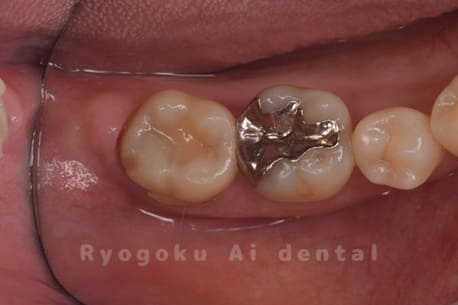

Case09

- 原因

- 左上6番重度カリエス

- 治療内容

- クラウンレングスニング

- 治療費用

- 44,000円(根管治療、補綴は別途費用)

他院で抜歯と判断された歯です。クラウンレングスニングを行い、保存を試みました。現在も問題なく被せ物が入り、使用できてます。

<リスク・副作用>

手術後は痛み、腫れ、痺れ、青あざなどの副作用が生じます。痛みは痛み止めを処方しますが、腫れ、青あざは1週間程度生じる場合があります。また、部位によっては神経の走行が複雑で、痺れが残り、長期的にお薬を処方する場合があります。